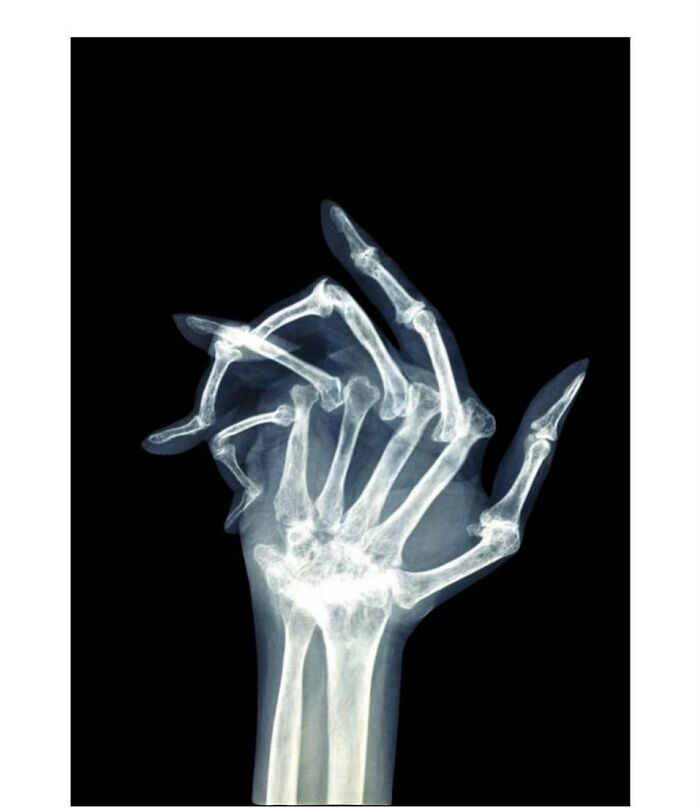

Plain radiograph of wrist joint shows polydactyly with duplication of ulna, duplication of ulnar side of carpal bones, metacarpals and phalanges, absence of radius and absence of thumb. Eight triphalangeal digits are seen. The middle phalanx of medial index finger is hypoplastic